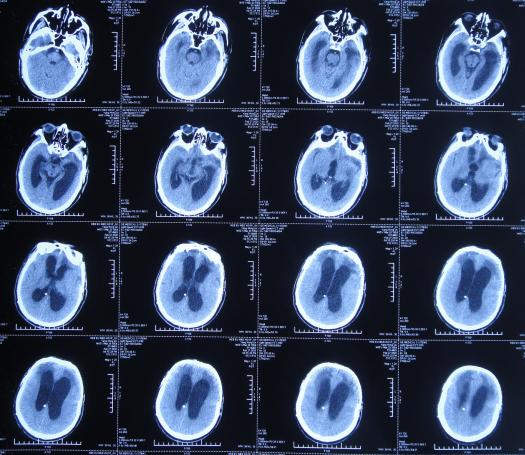

在第3家医院康复治疗近1个月时间内,曾4次查头颅影像(2020年1月22日( 图-24 )、2020年1月29日( 图-25 )、2020年2月10日( 图-26 )、2020年2月19日( 图-27 ))均示脑室仍有扩张,但未给予特殊处理。

图-24: 2020年1月22日头颅核磁

图-25: 2020年1月29日头颅CT

图-26: 2020年2月10日头颅CT

图-27: 2020年2月19日头颅CT

但住院期间间断性发热仅给予药物后仍反复,且大小便时有*禁失**,因此于第3家医院治疗28天后即2020年2月19日,转回当地的第4家河北省邯郸市某三甲医院治疗。

在第4家医院治疗26天,仍间断性发热、大小便*禁失**加重,住院期间曾2次查头颅CT(2020年2月27日( 图-28 )、2020年3月12日( 图-29 ))示脑室仍扩张。

图-28: 2020年2月27日头颅CT

图-29: 2020年3月12日头颅CT